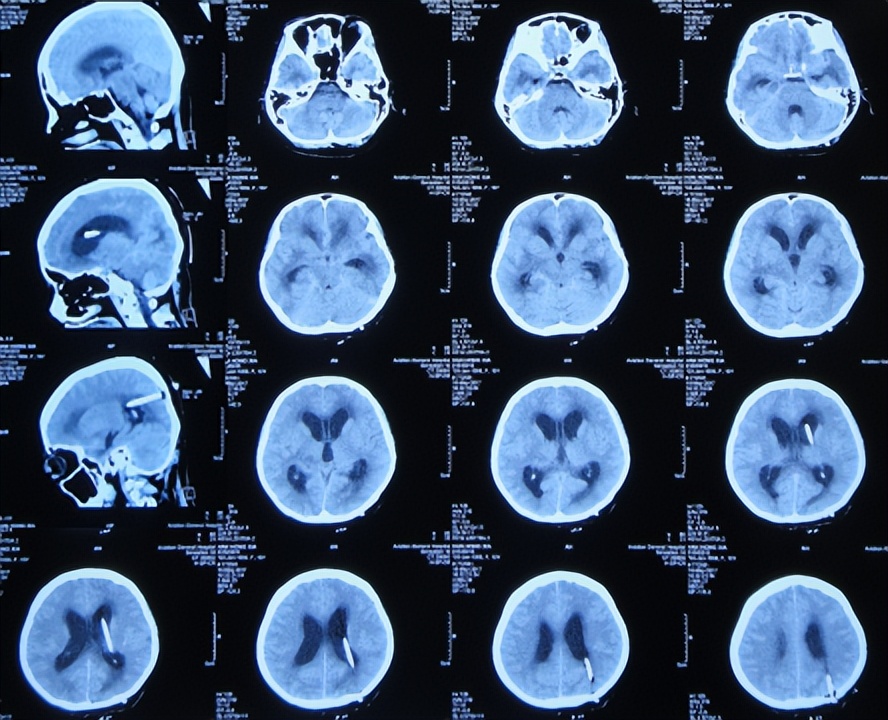

2017年4月26日(入院治疗24天),查脑增强核磁( 图-4 )后,继续给予相关抗感染治疗。

图-4: 2017年4月26日脑增强核磁

2017年5月8日(第4家医院入院治疗3天),查颈髓核磁未见异常( 图-6 )。

图-6: 2017年5月8日颈髓核磁